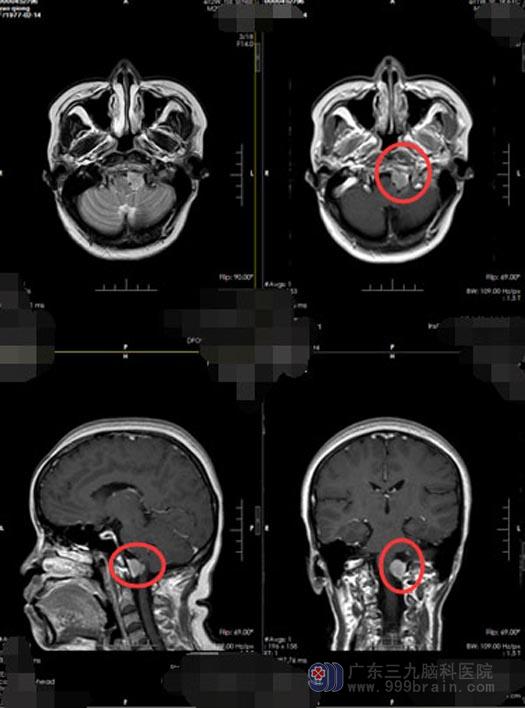

在众多家属的陪伴下,他们从四川来到了广东三九脑科医院神经外五科。头颅MR检查结果示:枕骨大孔区左侧占位性病变,考虑脊膜瘤,CTA检查结果示:枕骨大孔区左侧占位性病变,与椎动脉关系密切。经过之前多次被外院拒绝的经历,琼姐明白自己的手术难度有多大;主治医生林德留也多次告诉她,脑干延髓位置的手术是九死一生。

排除手术禁忌症后,由鲁明副院长主刀,神经外五科手术团队为姚阿姨施行“枕骨大孔区占位性病变切除术”。术中见灰白色肿瘤组织位于小脑内,内侧挤压脑干,显微镜下小心分离保留重要血管,可见其血供丰富,术中肿瘤全切。术后第二天,姚阿姨生命体征平稳,神志清楚,对答正确,四肢肌力肌张力正常,可遵嘱活动,无任何神经功能障碍与并发症,复查MR示:肿瘤全切,病理检验结果:枕骨大孔区纤维型脊膜瘤,WHO I 级,部分区域细胞增生活跃。经过二十多天的住院检查和治疗,目前已康复出院。